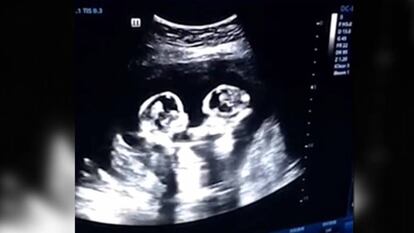

La ‘pelea’ de dos gemelas chinas en el vientre de su madre

Una ecografía muestra a los fetos de solo cuatro meses dándose con las manos y los pies

El vídeo de una ecografía realizada en Yinchuan, China, muestra a dos gemelas idénticas de tan solo cuatro meses dándose con las manos y los pies dentro del útero de su madre. La escena fue grabada por Tao, el padre de las niñas, durante un control rutinario a finales del año pasado. El padre explicó que las hermanas compartían el mismo saco amniótico y placenta, lo que es conocido como gemelos monoamnióticos monocroniales, una tipología de embarazo múltiple que presenta un mayor riesgo. Su tasa de supervivencia es inferior debido al mayor número de complicaciones que pueden producirse durante el embarazo. Algunos de los riesgos específicos que pueden darse son el enredo de los cordones umbilicales, compresión del cordón, nacimiento prematuro o la muerte intrauterina. Pero todo salió bien, ambas nacieron sin complicaciones el pasado 8 de abril por cesárea.